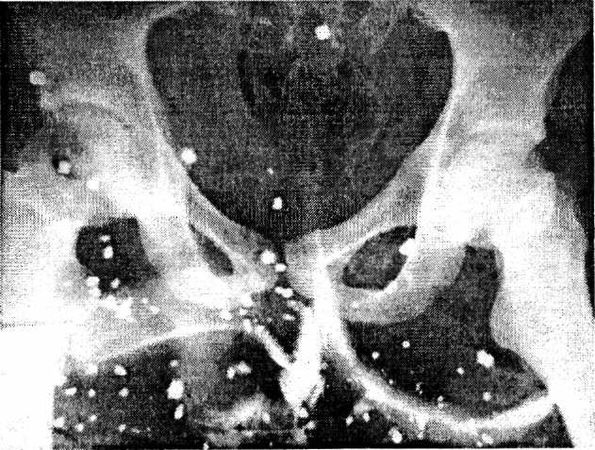

Осколочные раны характеризуются множественностью и различной площадью входных отверстий, хотя в настоящее время применяются боеприпасы, при взрыве которых образуются осколки определенной массы, размера и формы (рис. 2). Осколки современных снарядов обладают высокой начальной скоростью полета, которая может достигать 1500–2000 м/с, и большой кинетической энергией. Осколки, попадая в ткани, быстро передают энергию, так как полет их мало стабилизирован, то они часто вызывают слепые ранения. При сквозных ранениях наибольшая масса поврежденных тканей находится в области выходного отверстия, а сама рана имеет вид конуса, направленного в глубину [Беркутов А. Н., 1979, 1981].

Рис. 2. Множественные осколочные ранения живота и таза (рентгенограмма)